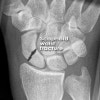

X-ray : 주상골 골절(Scaphoid fracture)

초기에는 X-ray 검사(AP/Lat/Scaphoid(Billiard view)이 기본)에서 나타나지 않을 수 있으므로 임상적으로 의심되는 환자는 초기 X-ray 검사를 척골 치우침 자세로 촬영합니다.

여기에서도 정상이면서 통증이 2~3주간 지속되면 반복해서 X-ray 검사를 하고(>10% of cases : Repeat imaging in 2 weeks will often show fracture) MRI 검사를 합니다.